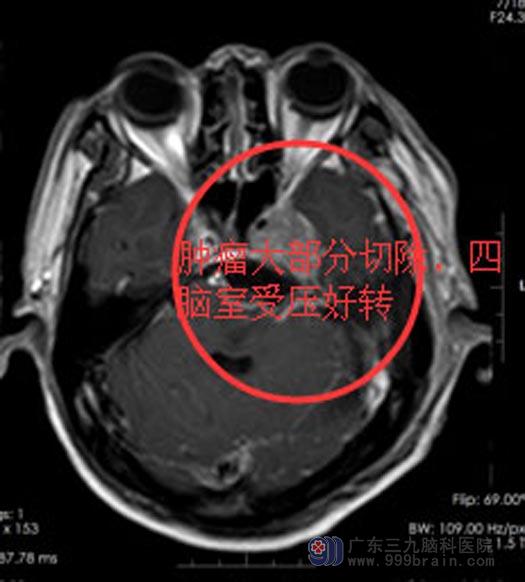

全麻下经左侧乙状窦后入路联合颞下入路行“左侧跨中后颅窝巨大肿瘤切除术+硬脑膜修补术+颅骨成形术”,术中见肿瘤上至三叉神经,下达末组颅神经,硬膜明显粘连。切除肿瘤大小约3cm×2cm×2cm,相邻神经、血管解剖保护满意,面听神经解剖保留。术后马先生未出现肢体活动障碍,无面瘫、听力下降等,由康复科介入为他进行吞咽功能训练。

现马先生恢复良好,饮水呛咳得到有效改善,可以自行进食,走路也恢复正常,没有留下后遗症。